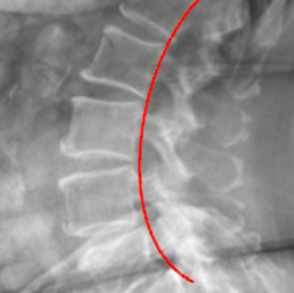

lumbar lordosis

George’s Line (Posterior Vertebral Body Line)